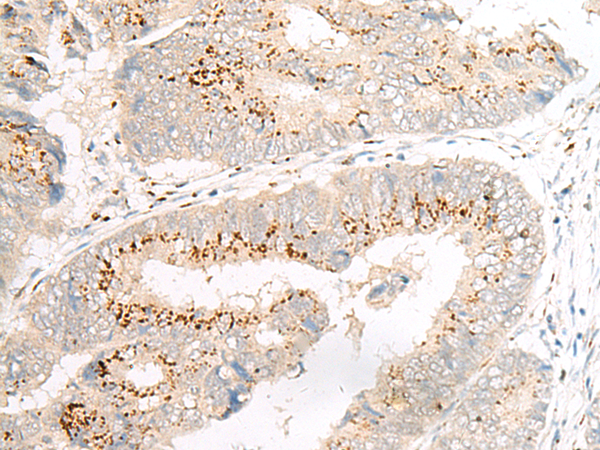

IHC positive control: |

Human colorectal cancer |

IHC Recommend dilution: |

20-100 |